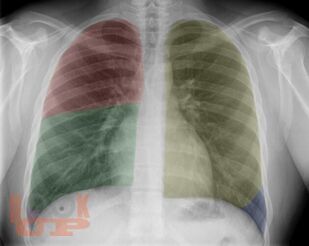

Рентгеноанатомия органов грудной клетки

В учебном пособии представлена информация о нормальной рентгеновской анатомии органов грудной полости, вариантной анатомии, наиболее частых аномалиях развития, скиалогии, алгоритме описания рентгенограмм и основных требованиях по оформлению протокола рентгенологического исследования.